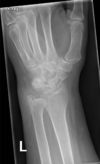

Fratura de Chaffeur

Fratura do processo estilóide do rádio.